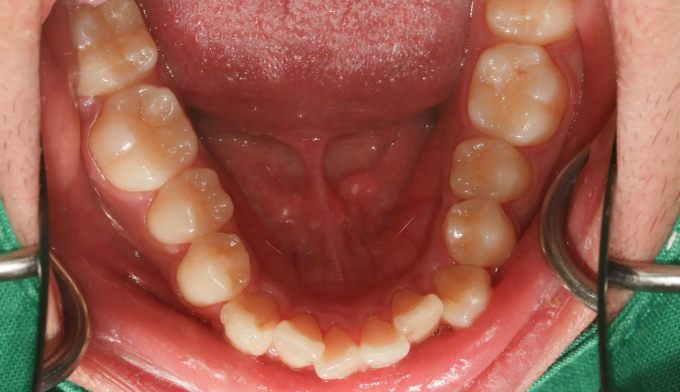

불규칙한 앞니를 교정하기 위해선 공간을 만들어야 합니다.

악궁이 좁은 경우에는 확장치료를, 그렇지 않으면 전체 치아를 후방이동시키거나 치아를 삭제하기도 합니다.

이번에는 악궁이 좁은 경우에 해당됩니다. 그 정도가 심해, 윗니 일부가 아랫니보다 안쪽으로 들어가있습니다.